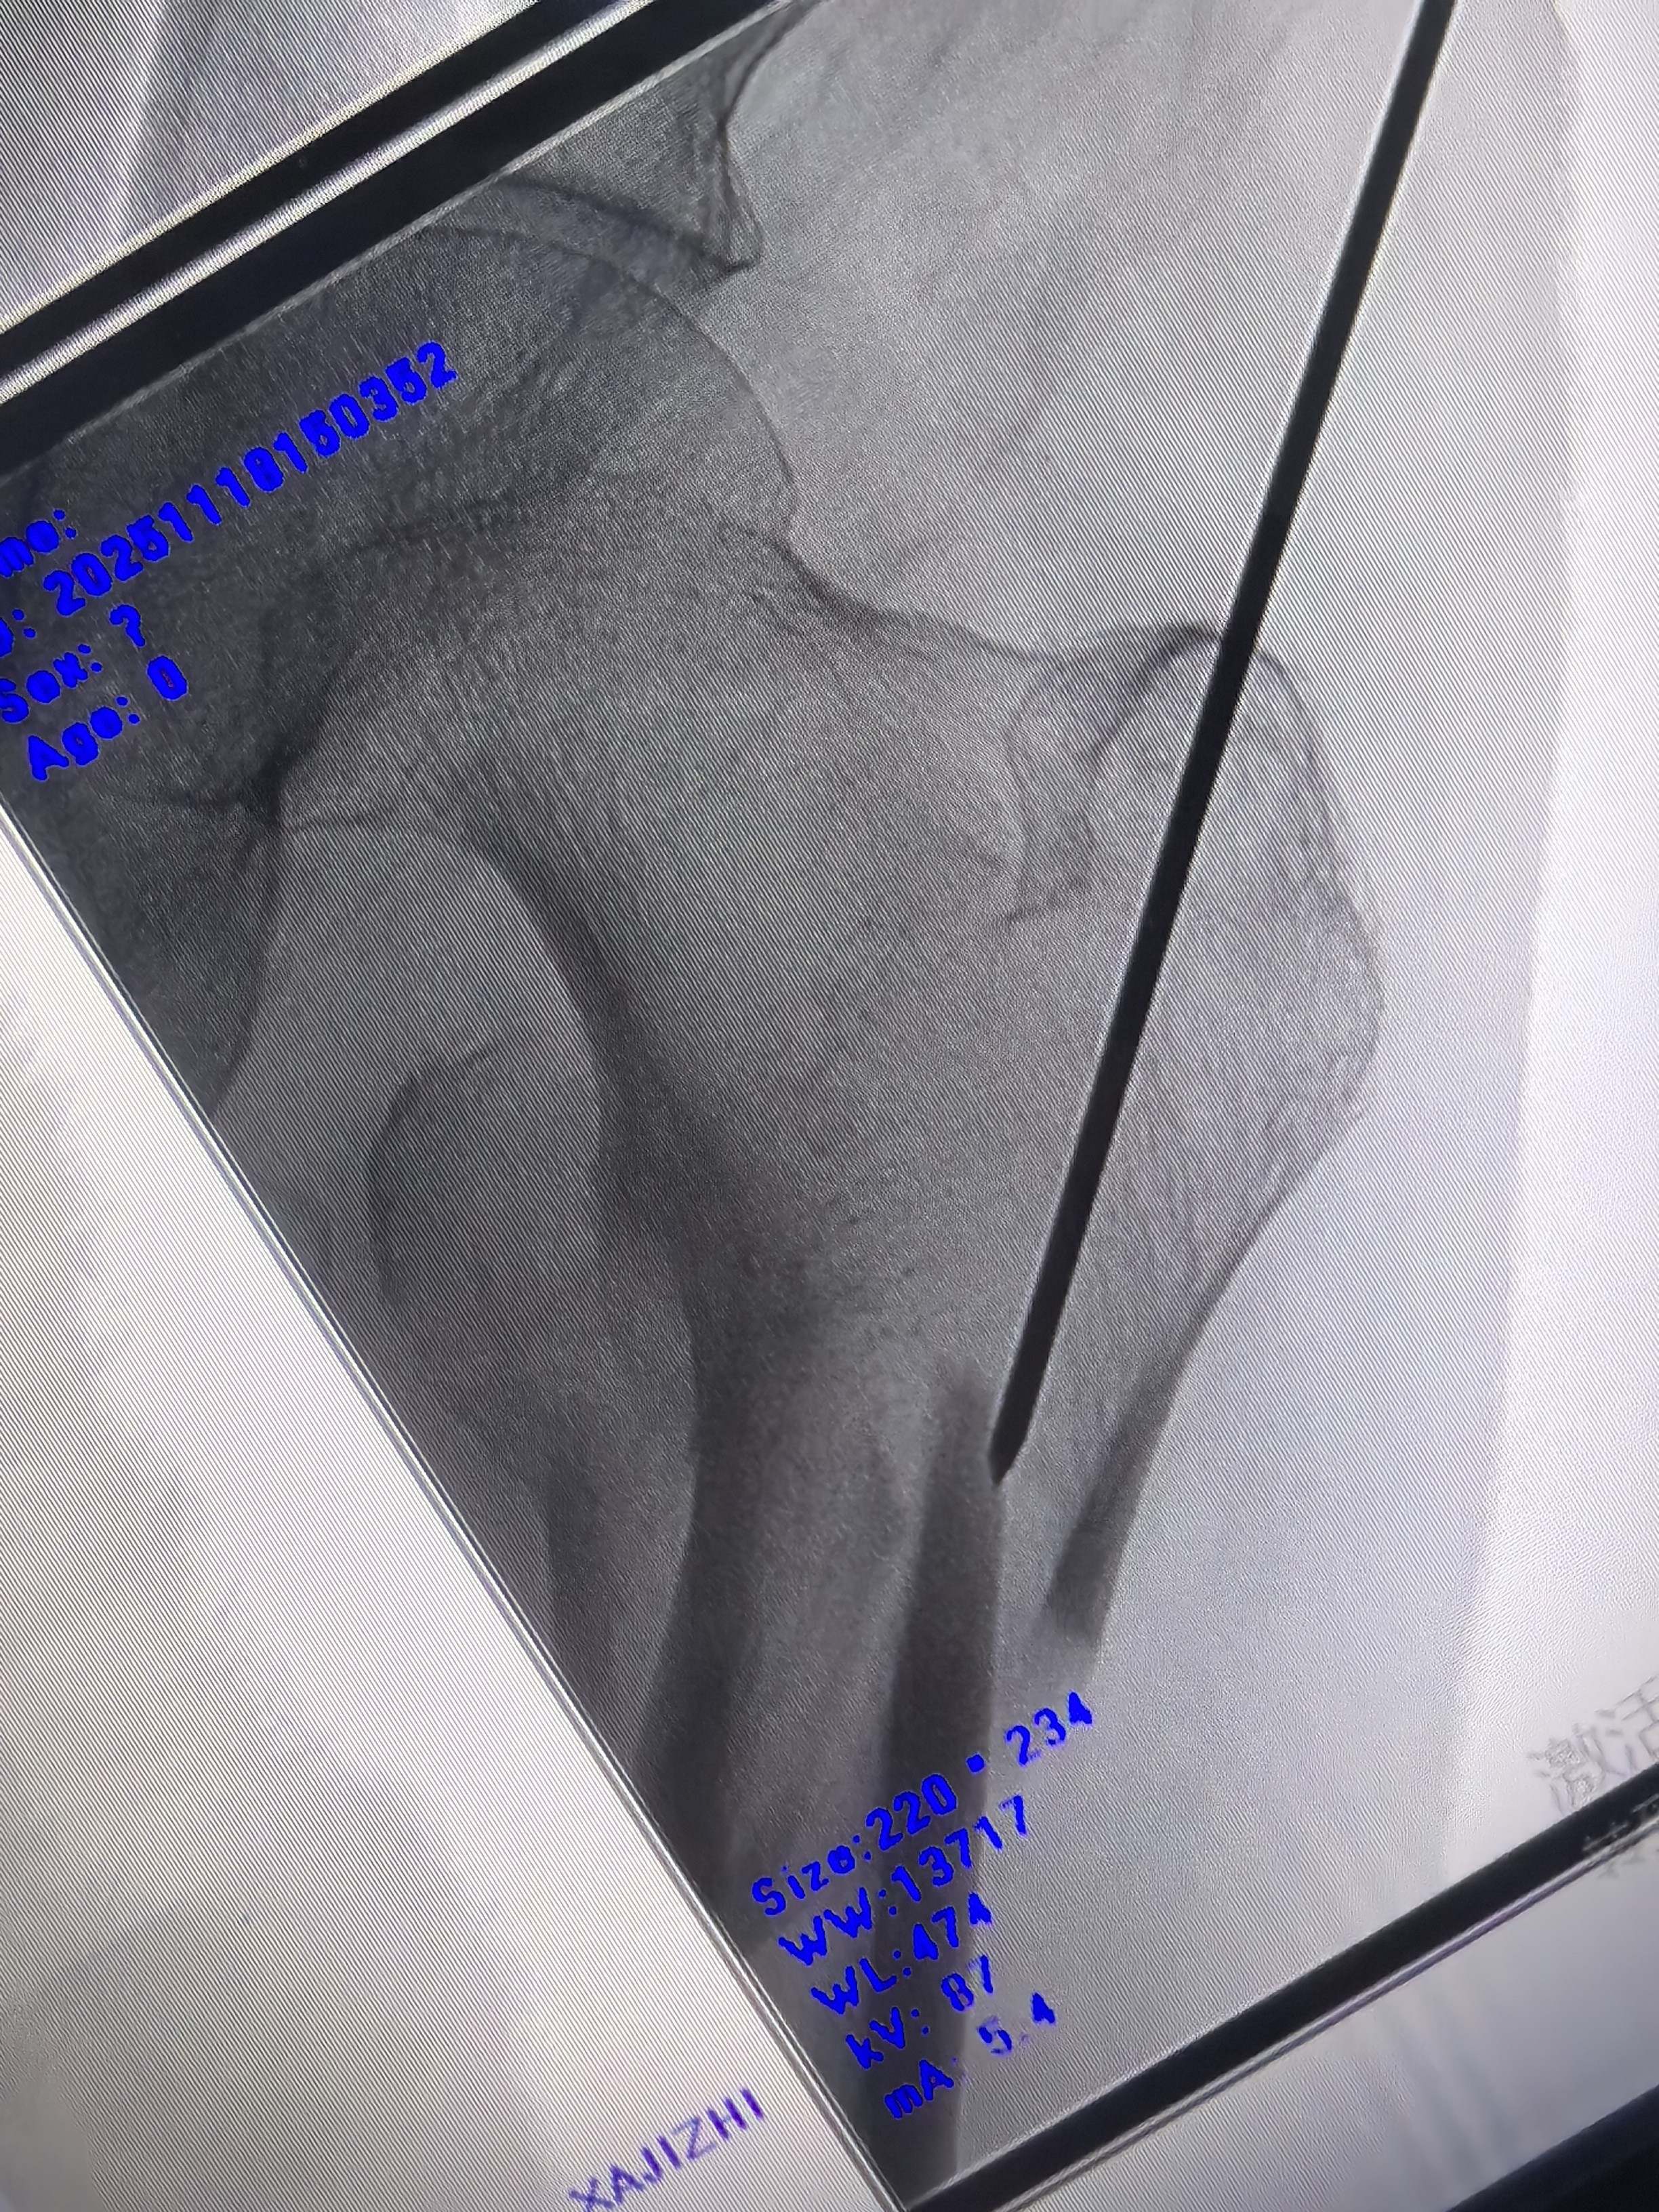

定位透视如下

轴位定位克氏针略偏后

正位还行,调整轴位克氏针定位